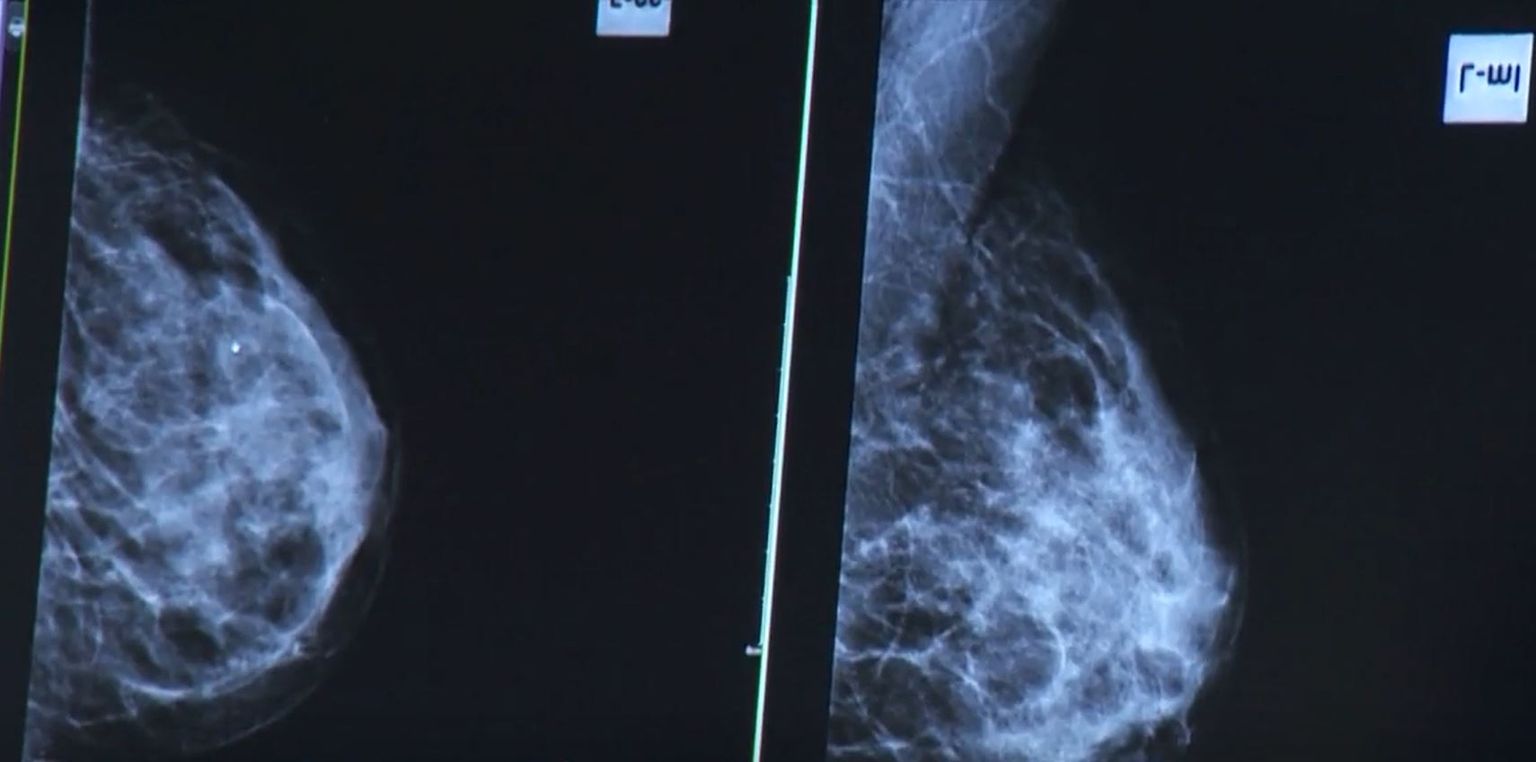

• Rano otkrivanje karcinoma - 1 Foto: DNEVNIK.hr

• Rano otkrivanje karcinoma - 2 Foto: DNEVNIK.hr